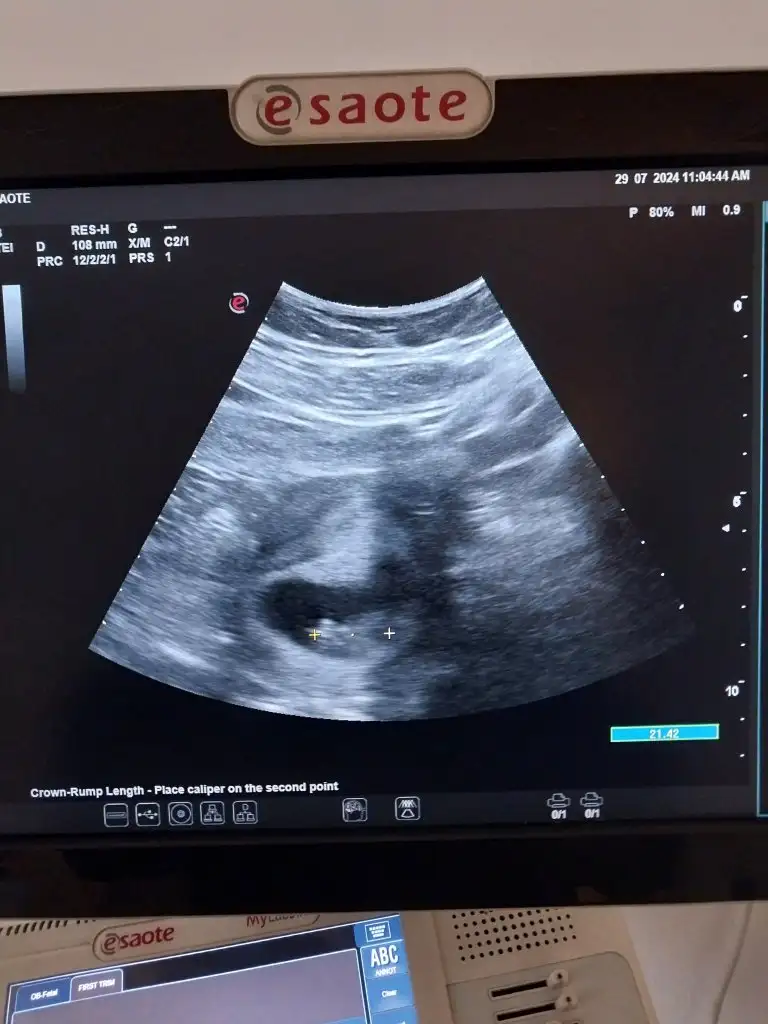

9 hafta 3 günlük böyle çıktı :KK70: çok küçük değil mi 2 cm olmalı yazıyo uygulamada ama burda 108 mm görünmüş

Belki tam baştan popoya ölçmemiştir burada, sanki sağa dogru biraz daha büyükmüş gibi geldi bana :) boyu ne kadarsa da daha büyüyecek annesi inşallah takılma sen 😍